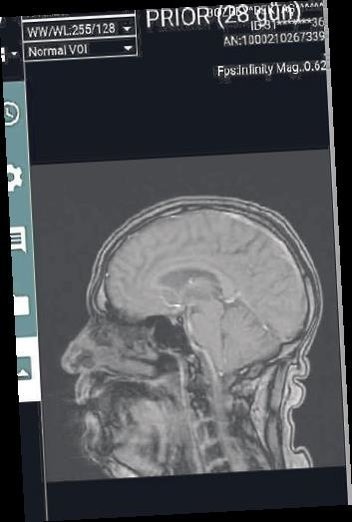

Yeşilçam'ın efsane oyuncusu Kemal Sunal'ın unutulmazları arasında yer alan Korkusuz Korkak filmi Balıkesir'de gerçek oldu. 17 yaşındaki Bektaş Bozbey'in MR görüntüleri, 80 yaşlarındaki başka bir hastanın MR görüntüleri ile karıştı.

Türk sinemasının efsane ismi Kemal Sunal'ın oynadığı Korkusuz Korkak filmi, Balıkesir'de gerçek oldu… Yeni Asır'ın haberine göre; Eylül ayında el titremesi şikayetiyle Atatürk Şehir Hastanesi'ne giden 17 yaşındaki Bektaş Bozbey'in MR filmleri, başka bir hastanın görüntüleri ile karıştı.

80 yaşlarındaki bir başka hastaya ait olduğu belirlenen görüntülerde ciddi hastalıklar tespit edilmesi sebebiyle Balıkesir Çocuk Nöroloji Doktoru İ.D.Ç'nin isteği üzerine Bektaş Bozbey, Bursa'daki bir hastaneye sevk edildi.

Kendi imkanları ile Bursa'daki hastaneye giden Bektaş Bozbey ve ailesi, buradaki Çocuk Nöroloji Uzmanı Cengiz Havalı'nın dikkati sayesinde skandal karışıklığı öğrendi. Ciddi bir rahatsızlığı olmadığı ortaya çıkan Bektaş Bozbey'in, Balıkesir Atatürk Şehir Hastanesi'nde çekilen MR'ı başka bir hastanınkiyle karıştırılmıştı.